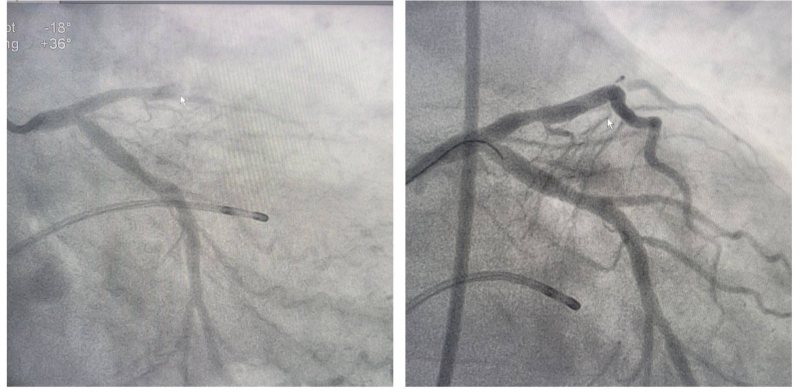

Hình ảnh các nhánh mạch vành tắc trước can thiệp (trái) và được tái lưu thông sau can thiệp (phải)

Kết quả chụp mạch vành bằng hệ thống chụp mạch số hóa xóa nền DSA cho thấy tổn thương tắc hai trong ba nhánh mạch vành – tắc hoàn toàn động mạch liên thất trước, tắc gần hoàn toàn động mạch vành phải, có nhiều huyết khối. Ekip can thiệp do Ths.BS Đinh Danh Trình đã thực hiện kỹ thuật can thiệp hút huyết khối, đặt 2 stent vào động mạch liên thất trước và động mạch vành phải để nong tổn thương hẹp, tạo hình mạch vành, tái thông dòng chảy cho mạch vành tưới máu cơ tim cải thiện. Ngay sau can thiệp, bệnh nhân thoát nguy kịch, được điều trị hồi sức tích cực, không còn đau tức ngực, huyết động ổn định.